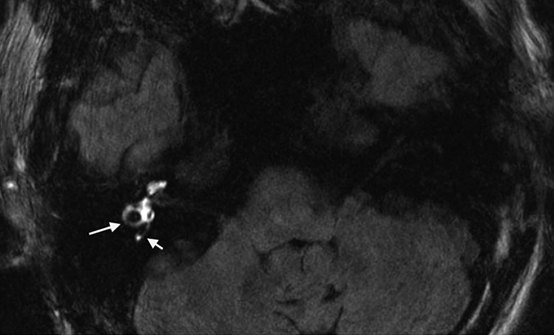

4、随着高分辨率核磁共振成像MRI的发展以及内耳局部给药技术的实现,在MD患者中观察到内淋巴积水已成为现实。2007年Nakashima等提出向MD患者鼓室中注射稀释的钆剂,24h后进行内耳三维磁共振成像液体衰减反转恢复序列3D-FLAIR MRI检查,由于造影剂可以经鼓室内侧壁渗透至外淋巴系统,而不能渗透至内淋巴系统,含有钆剂的外淋巴间隙显示为高信号,不含钆剂的内淋巴间隙显示为低信号,从而获得内淋巴积水的客观诊断依据。

耳蜗积水的分级标准——均以耳蜗底圈的截面部分为代表,耳蜗外淋巴间隙显示为造影剂渗入的高信号,内淋巴间隙显示为无造影剂的低信号。然后根据积水的情况进行分级,Nakashima于2009年提出内淋巴积水分级标准。其根据内淋巴间隙面积占同侧内耳间隙总面积(内、外淋巴间隙面积的总和)的比值R,以及耳蜗前庭膜的移位情况,将膜迷路积水的影像学诊断标准分为3级。2011年Gurkov等提出不同于Nakashima 的耳蜗积水分级标准,将耳蜗积水分为0、1、2、3共四级)。